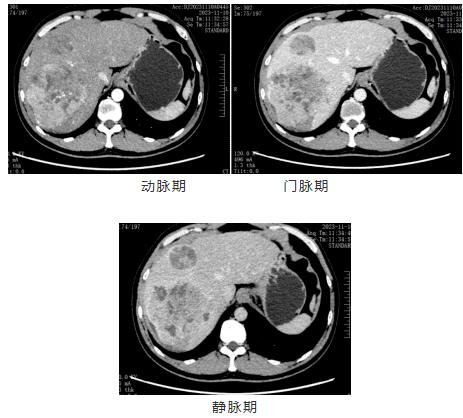

影像资料

诊断:肝恶性肿瘤(CNLCIIb)乙型肝炎肝硬化。